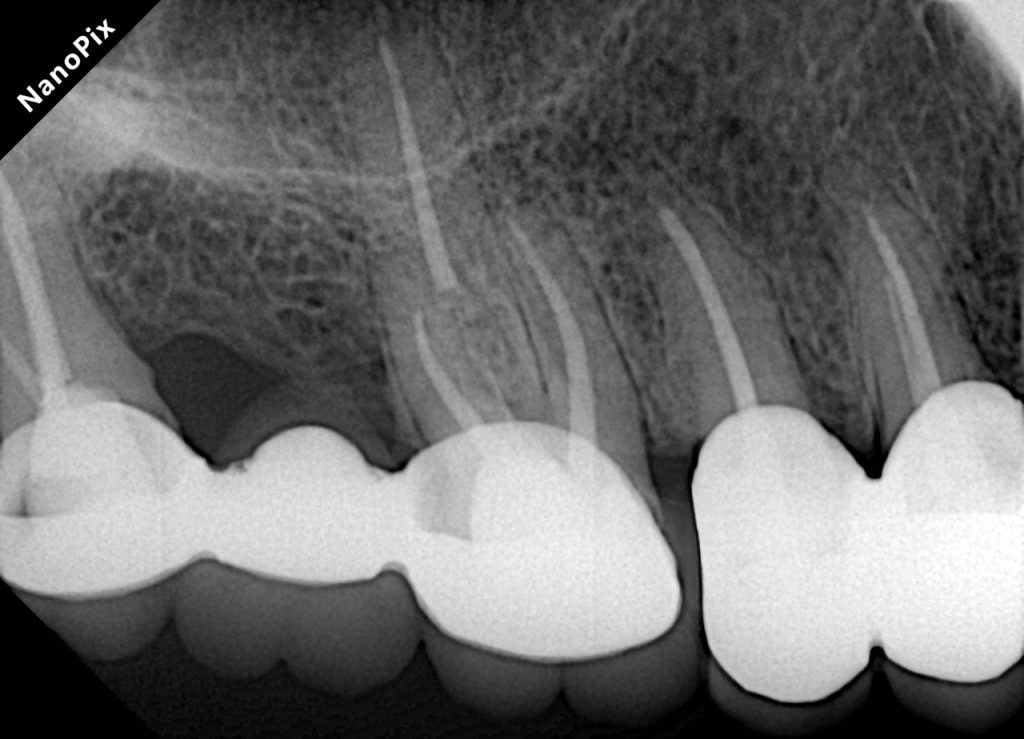

FIVE-YEAR FOLLOW-UP

At 5 years:

- Tooth structure remained intact

- Prosthetic margins were stable

- Periapical radiographic healing was evident

- Patient remained asymptomatic

- Excellent gingival response observed

- No secondary caries or debonding

- Occlusion stable and functional

✅ Long-term quadrant stability achieved